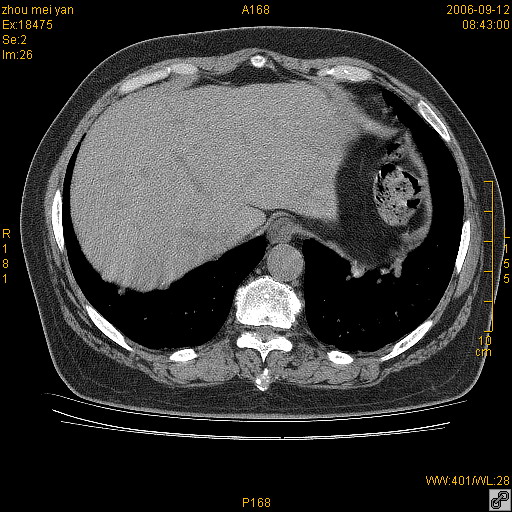

患者、女、55岁。因心率失常住院检查ct发现胸部多发结节。腹部b超肝、胆、胰、脾、肾、子宫附件未见异常。无结核病史,无粉尘接触史。请大家来会诊。谢谢!

病变位于胸膜,多发结节,边界清楚,内见小结节状钙化。其它未见异常。

双侧胸膜多发结节,形态不规则,边缘较清楚,每一个结节中心似乎都有钙化点的特征,与胸膜广基相切。临床无结核病史,无粉尘接触史。

影像表现十分有特点:双侧肋胸膜及膈胸膜广泛散在分布大小在2至6mm左右,较大病灶中心可见钙化。

考虑恶性胸膜间皮瘤可能性大,病灶位于胸膜,以宽基地与胸膜相连,呈结节样改变,部分病灶内可见点状钙化影。请各位老师多多指导!

双侧肋胸膜及膈胸膜广泛散在分布大小不等结节影,较大病灶中心可见钙化。